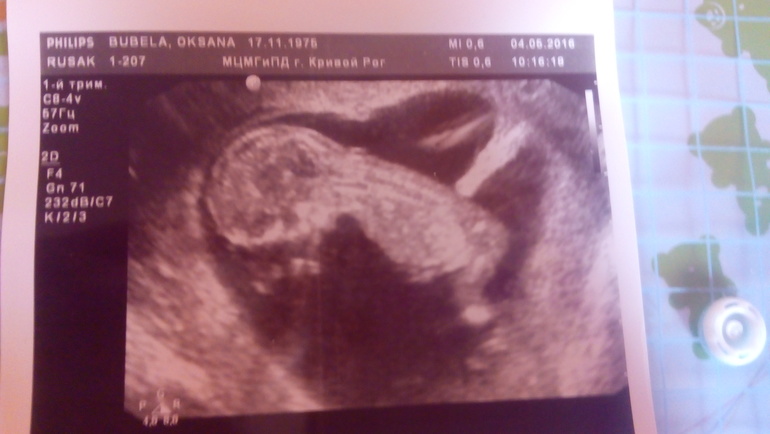

Малышочек такой прекрасный!!! Хороший человек растёт - сразу видно!!! 💕 💋

Да,уже человечек,бракался,уворачивался,не давал посчитать сердцебиение))) как ты? Простуда полностью прошла?

Да,сказали предположительно мальчик...Я делала скрининг в генетическом центре,один из лучших у нас в стране,и врачи там квалифицированные.